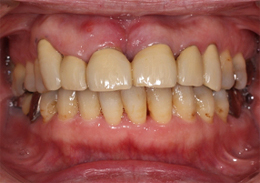

- 主訴

- 上顎前歯の噛む時の痛み

- 治療内容

- 上顎前歯部を抜歯すると大きな骨吸収を予測したため、下顎臼後三角部より骨片を採取し、抜歯時にインプラント埋入と同時に骨造成を行なった

- 治療費用

- 800,000円(税別)

- 治療期間

- 5ヶ月